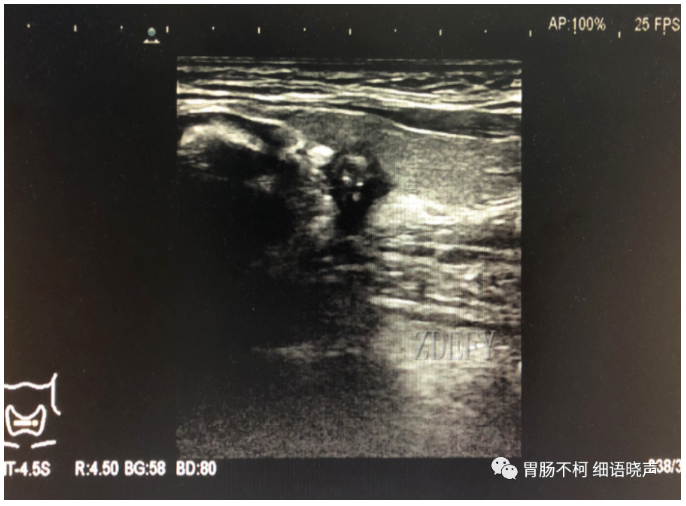

病例二:甲状腺左叶后方强回声型咽食管Killian-Jamieson憩室(此病例由杭州市第一人民医院韩志江主任提供)。

食道左侧壁见一囊袋状突起,边缘光滑。